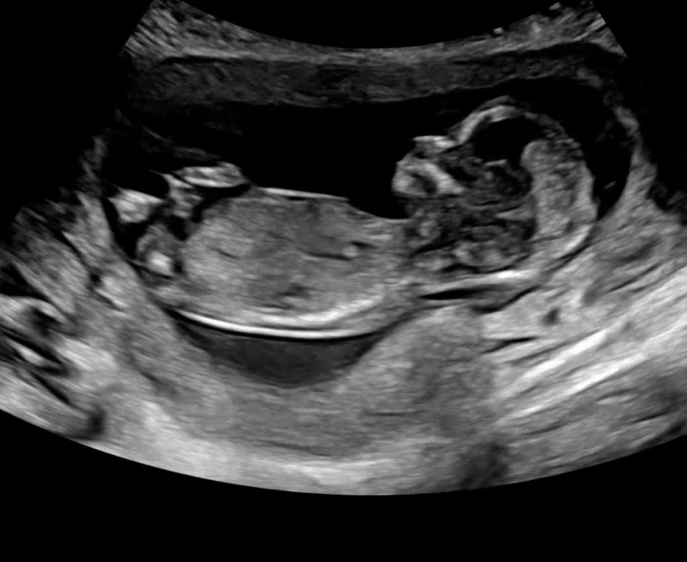

✨임신19-23주차일상/정밀초음파/전치태반/임산부수영/

20주-24주차에는 태아 정밀 초음파를 보는 시기예요 1차검진때 목투명대 등 기본 검사를 했다면 정밀초음파...